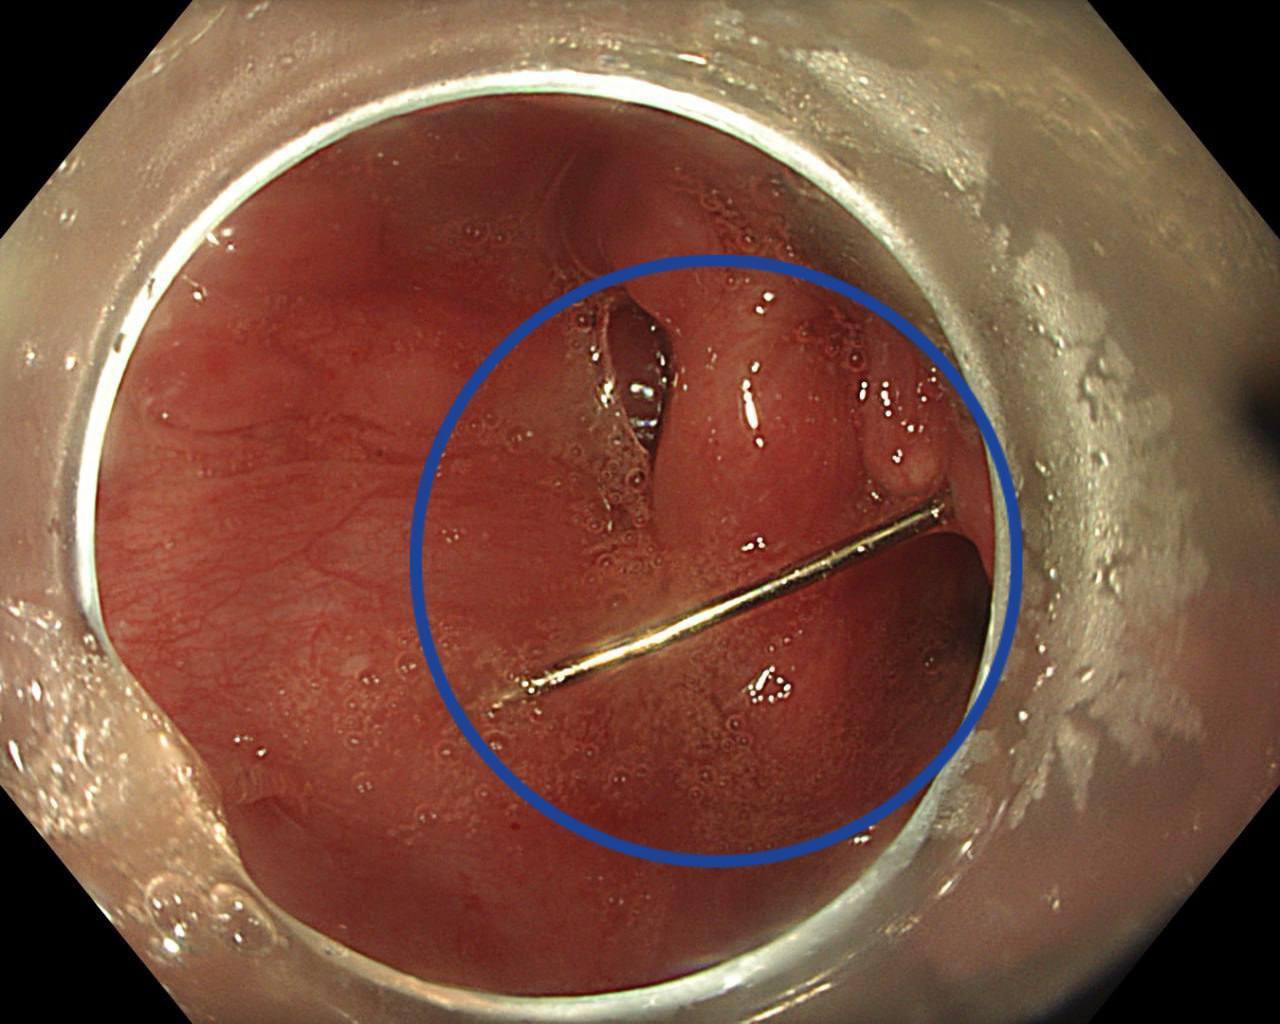

Пациентку доставили в Детский научно-клинический центр им. Л.М. Рошаля с жалобами на сильную боль в горле, рвоту с кровью и затрудненное глотание. Врачи при обследовании обнаружили инородное тело:

«Мы выполнили пациентке эндоскопическую операцию по удалению инородного тела: с помощью эндоскопических щипцов, клинка для прямой ларингоскопии и хирургического зажима аккуратно захватили иголку и извлекли из гортаноглотки.

Операция прошла успешно и без единого разреза», — сказал заведующий отделением эндоскопических методов диагностики и лечения Александр Иноземцев.